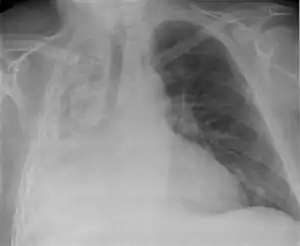

![]() Тотальний ателектаз правої легені (вид спереду) Тотальний ателектаз правої легені (вид спереду) | |

Досить часто у хворих можуть бути прояви попереднього ураження легень. При гострому виникненні значного ателектазу хворі можуть відчувати біль у грудній клітці, посилення задишки; при обстеженні хворого відмічають ціаноз, невелике відставання при диханні ураженої половини грудної клітки, приглушення перкуторного звуку у відповідній ділянці легені, там же послаблення дихання та голосового дрижання. Можуть бути тахікардія, гіпотонія, при ускладненні ателектазу інфекцією — підвищення температури тіла. Однак часто при поступовому розвитку ателектазу та невеликих його розмірів клінічні симптоми можуть бути несильно виражені, та ателектаз діагностують рентгенологічно. При цьому прозорість ураженої ділянки легені зменшується, тінь її часто має трикутну форму з верхівкою, оберненою до кореня легені. При великому ателектазі може бути зміщення органів в уражену сторону. Своєрідною формою ателектазу є так званий синдром середньої частки, зумовлений обтурацією великого бронха збільшеним лімфатичним вузлом. Найчастіше цей лімфатичний вузол є проявом туберкульозу — туберкульоз внутрішньогрудних лімфатичних вузлів. Для уточнення причини іноді доводиться проводити томографію, бронхографію.